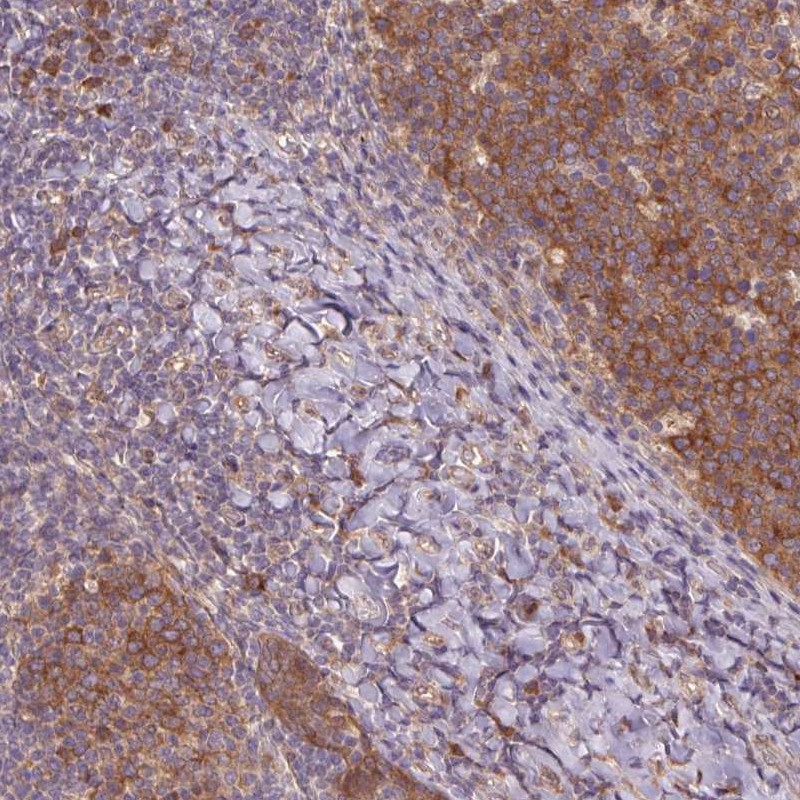

Immunohistochemical staining of human tonsil shows cytoplasmic positivity in germinal center.